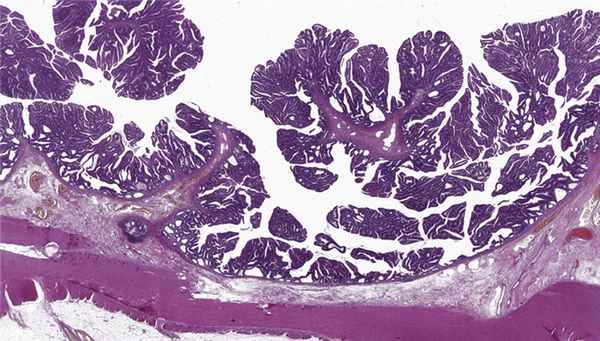

Данные морфологического исследования: в слизистой толстой кишки на всем протяжении имеются множественные тубулярные (преимущественно) и тубуло-ворсинчатые аденомы со слабой дисплазией эпителия, большое количество аберрантных крипт и микроаденом со слабой дисплазией эпителия. Крупная циркулярная опухоль в прямой кишке — ворсинчатая аденома со слабой и очаговой умеренной дисплазией эпителия. Морфологическое заключение: морфологическая картина семейного аденоматоза толстой кишки (рис. 4). Рис. 4. Морфологическое исследование: cтенка толстой кишки с множественными аденомами. Окраска: гематоксилином и эозином.